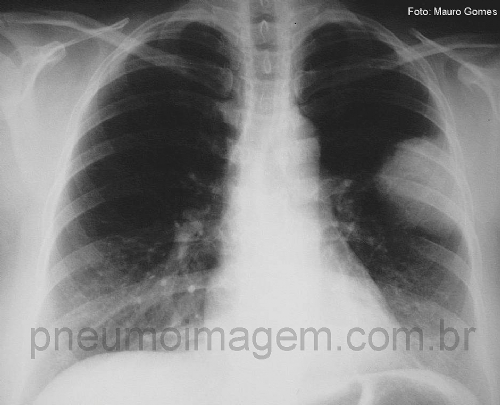

CASO CLÍNICO #23Homem, 46 anos, apresenta-se com tosse seca há 3 semanas acompanhada por dispneia leve aos esforços. Nega febre e perda de peso. Tabagista por 20 anos/maço. Observe atentamente a radiografia de tórax, faça suas hipóteses diagnósticas e deixe seus comentários.

Man, 46, presents with dry cough for three weeks accompanied by mild dyspnea on exertion. Denies fever and weight loss. Smoker for 20 pack / year. Look closely chest X-ray, make your diagnostic hypotheses and enter your comments.